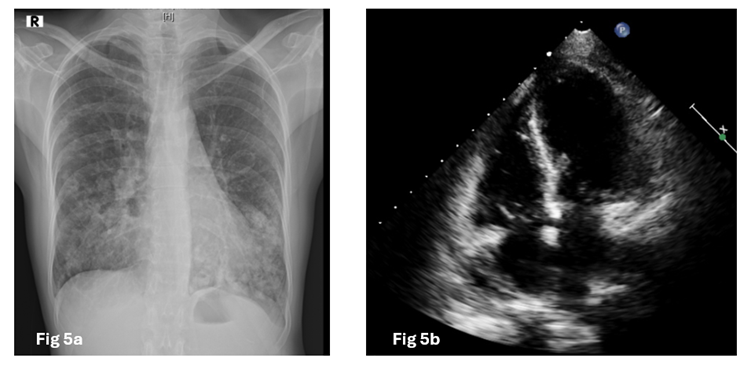

Next day the patient developed a pleuritic chest pain with respiratory distress with hypotension. Follow up chest radiograph showed a lucency around the cardiac silhouette with 'continuous diaphragm sign', limited superiorly by the cardiac pedicle, which was not seen in previous radiograph with reduction in cardiac size. (Figure 3). Emergency CT Thorax revealed pneumopericardium. (Fig 4) In view of pneumopericardium with hemodynamic compromise she was taken up for pericardiocentesis again and final flouro showed minimal residual air in the pericardial cavity. Recheck echo showed normal biventricular function and no features of cardiac tamponade. Subjective symptoms and radiological signs of pneumopericardium disappeared five days later. (Fig 5) The patient’s clinical syndrome was treated with steroids and antitubercular therapy.

Figure 5a: (Chest radiograph) 5b (Transthoracic echo) showing no signs of pneumopericardium.